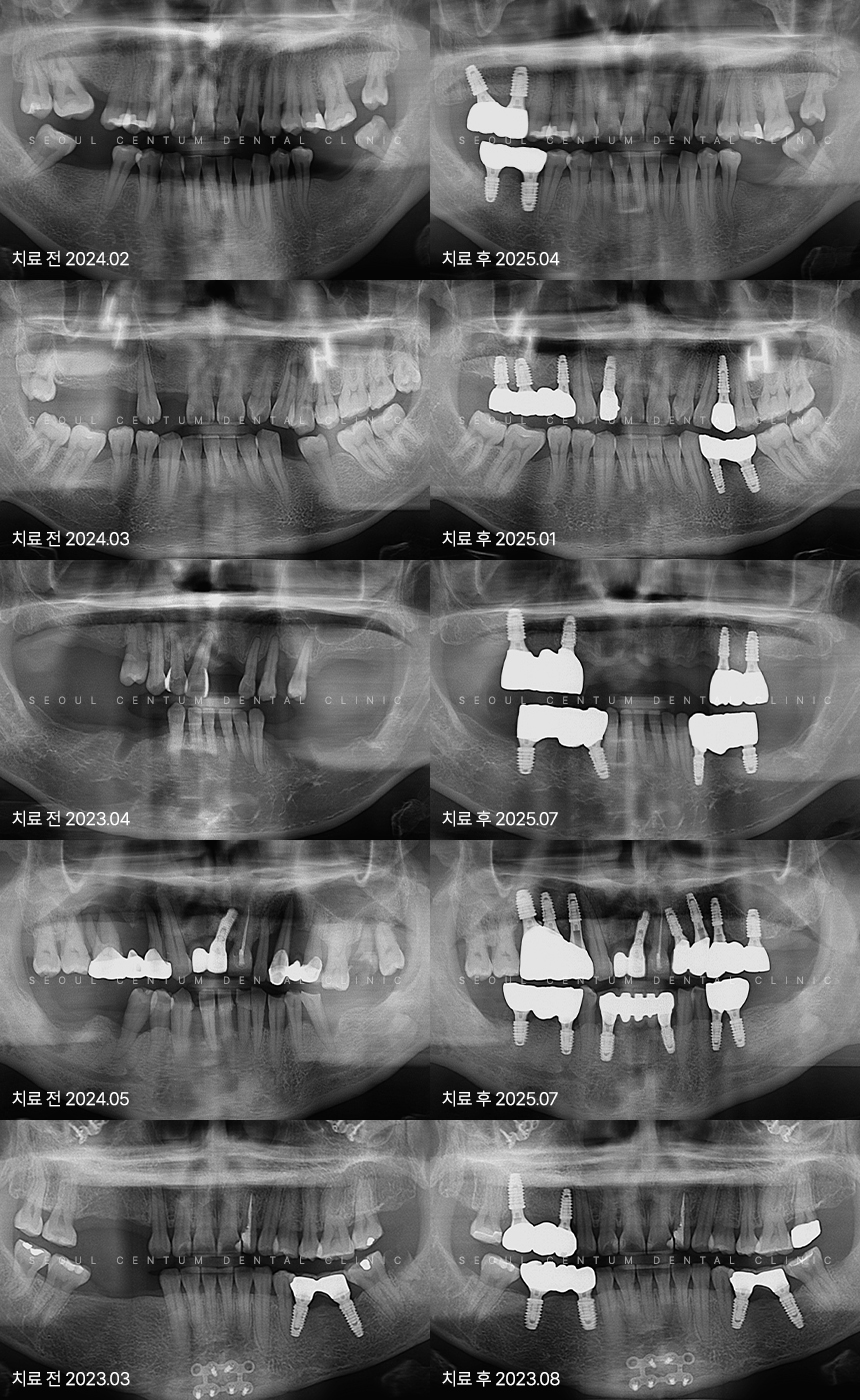

임플란트 실제 사례